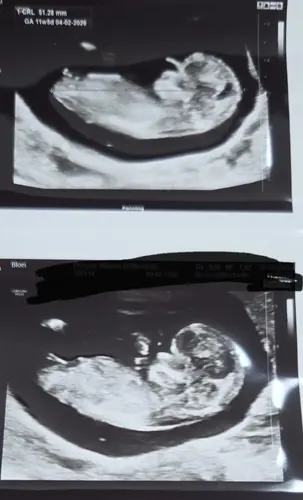

Pas 11 weken, maar de verloskundige dacht al wel een meisje te zien, maar zei erbij dat we er nog niet vanuit kunnen gaan (al had ze het de laatste tijd wel steeds goed bij anderen). Ik dacht zelf eigenlijk ook duidelijk een meisje te zien. Ben benieuwd :)

13 weken en 1 dag, ben heel erg benieuwd of jullie al iets kunnen zien😊